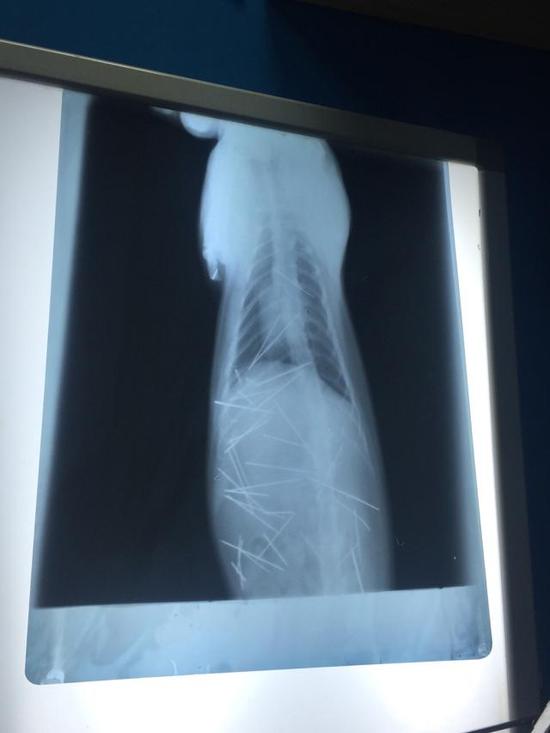

X光图片X光图片

这是一个残忍而又暖心的故事。一位小姑娘发现她收养一年的小猫脖子后有凸起,到医院检查发现,小猫体内有多达30至40根针。广州某宠物医生判断,这些针不是手工插入,很有可能是用类似气枪的东西打入的。5月21日夜,手术完成,医生用了近4小时的时间,取出了43根针(包括断掉的针头)。主人表示,很多针都已经生锈。

这位生活在深圳的小姑娘是5月19日发现小猫异常的,她在当晚发出的微博有多张小猫的X光照片,其中密密麻麻的针看起来十分恐怖。观察者网注意到,她的这条微博已有3万余次转发。次日(20日),她带小猫来到深圳某宠物医院治疗,因为该院没有C型臂,所以又转至广州一家宠物医院。21日夜手术结束后,该宠物医院表示,7根针是在皮肤或肌肉,3根针和2个断端在胸腔心脏旁边。30根针在腹腔,其中有4根是插入到左侧肾脏。这是一个复杂的手术,为了这个可怜猫猫,X线连续曝光53次。